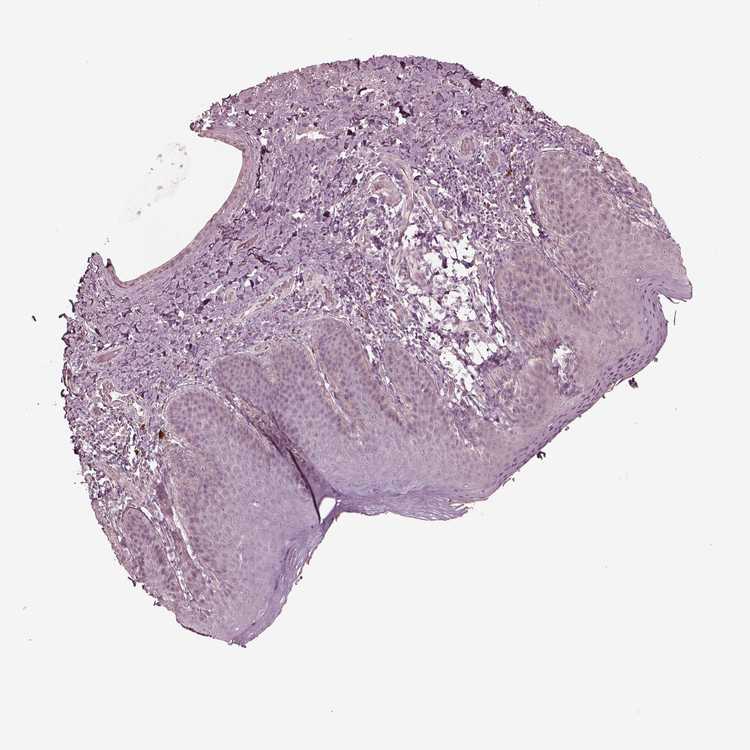

SKIN 2 - Antibody stainingi

Antibody staining in the annotated cell types in the current human tissue is reported as not detected, low, medium, or high, based on conventional immunohistochemistry profiling in selected tissues. This score is based on the combination of the staining intensity and fraction of stained cells.

Each image is clickable and will lead to virtual microscopy that enables deeper exploration of all samples and also displays staining intensity scores, fraction scores and subcellular localization as well as patient and tissue information for each sample.

Antibody HPA038811

Epidermal cells Not detected